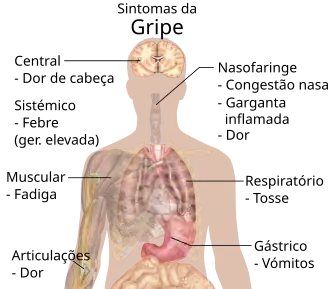

Os sintomas de gripe podem ter início de forma súbita um ou dois dias após a infeção. Geralmente, os primeiros sintomas são calafrios ou uma sensação de frio, embora a febre seja também comum nesta fase, com temperaturas entre os 38 e os 39 °C.[19] Muitas pessoas sentem-se de tal forma doentes que se sentem compelidas a ficar de cama por vários dias, com dores ao longo de todo o corpo que se agravam nas costas e pernas.[20] Os sintomas da gripe podem incluir:

- Febre e sensação extrema de frio (calafrios e tremores)

- Tosse

- Congestão nasal

- Rinorreia

- Dores musculares, principalmente nas articulações e na garganta

- Fadiga

- Dores de cabeça

- Olhos irritados e lacrimejantes

- Vermelhidão nos olhos, boca, garganta e nariz

- Petéquia[21]

- Em crianças, sintomas gastrointestinais como diarreia e dores abdominais,[22][23] que podem ser graves nos casos de gripe B,[24] ou ainda provocar náuseas e vómitos.[20]

Nos primeiros estágios de infeção, pode ser difícil distinguir uma gripe de uma constipação.[8] A gripe pode ser identificada pelo aparecimento súbito de febre elevada e fadiga acentuada. A gripe é uma mistura de sintomas de constipação e de pneumonia, dores musculares, dores de cabeça e fadiga. Em adultos, a diarreia normalmente não é um sintoma de gripe,[17] embora tenha sido observada em alguns casos de gripe aviária[25] e possa ser um sintoma em crianças.[22] Os sintomas de maior fiabilidade para determinar um diagnóstico de gripe encontram-se na tabela à direita.[17]